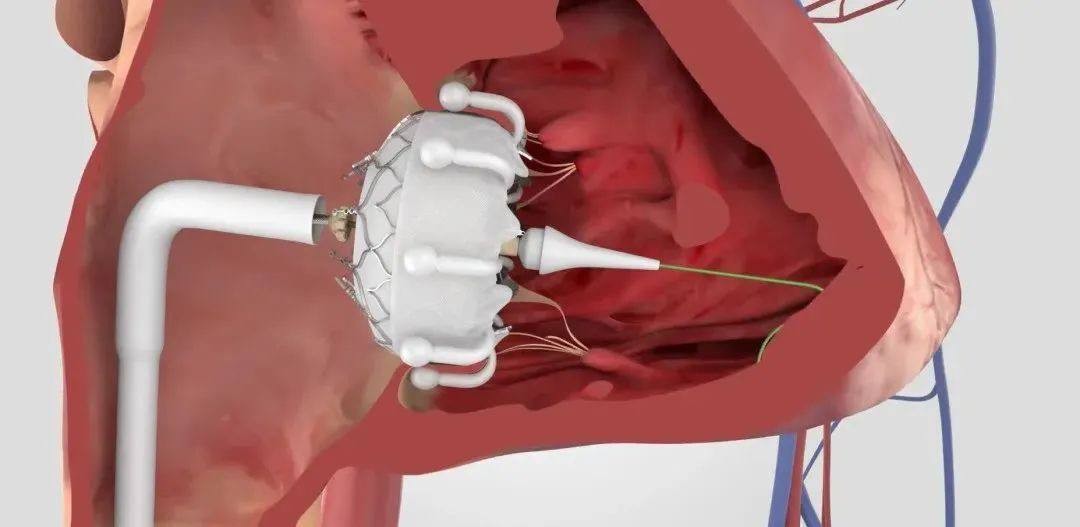

新一代MitraClip与TriClip G5系统

项目类型

器械质押区

起投金额

10000USDT

每日释放:0.9

释放周期:45 天

已购: 10000

剩余: 0

Evoque|爱德华生命科学

项目类型

医疗器械区

起投金额

9000USDT

每日释放:0.9

释放周期:60 天

已购: 10000

剩余: 0

SAPIEN 3 Ultra RESILIA|爱德华生命科学

项目类型

器械质押区

起投金额

4000USDT

每日释放:0.85

释放周期:85 天

已购: 20000

剩余: 0